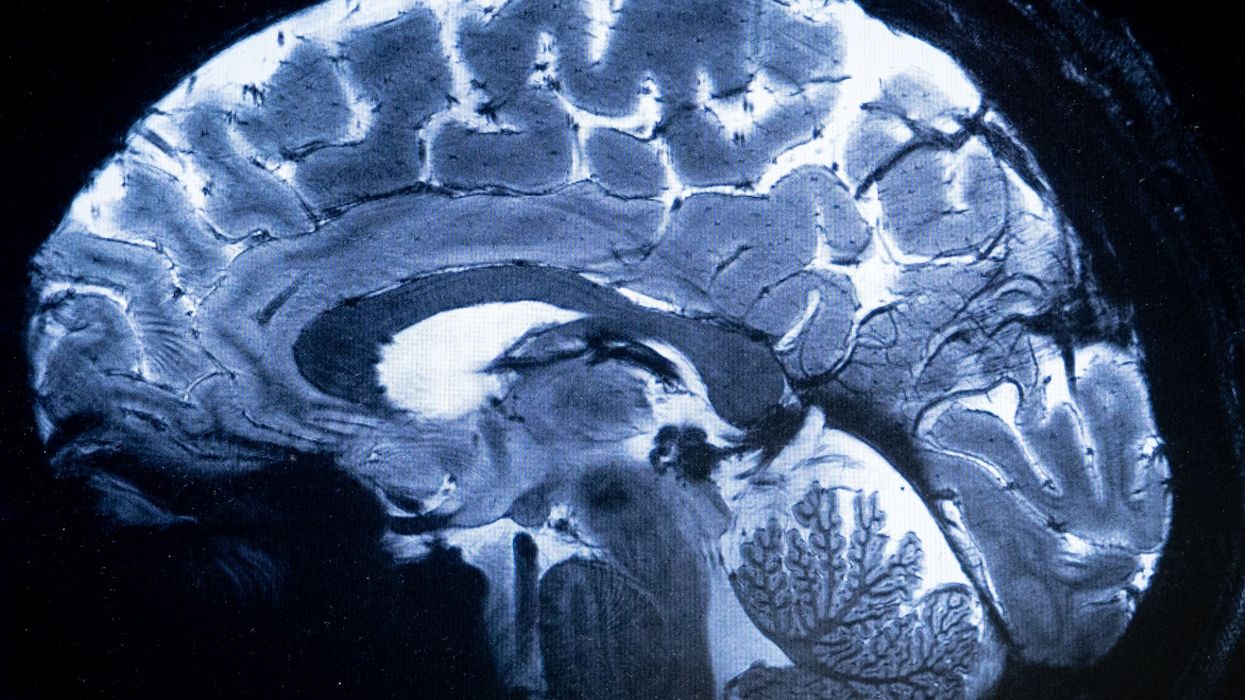

Climate change is likely to negatively affect the health of people suffering from brain conditions such as migraine and Alzheimer's, new research published in The Lancet Neurology journal has found.

Extreme temperatures, both low and high, and greater changes over the course of the day -- driven by climate change -- were shown to have an impact on brain diseases, explained lead researcher Sanjay Sisodiya from the University of College London's Institute of Neurology, UK.

The study, reviewing 332 papers published from around the world between 1968 and 2023, looked at 19 different nervous system conditions, including stroke, migraine, Alzheimer's, meningitis, epilepsy and multiple sclerosis.